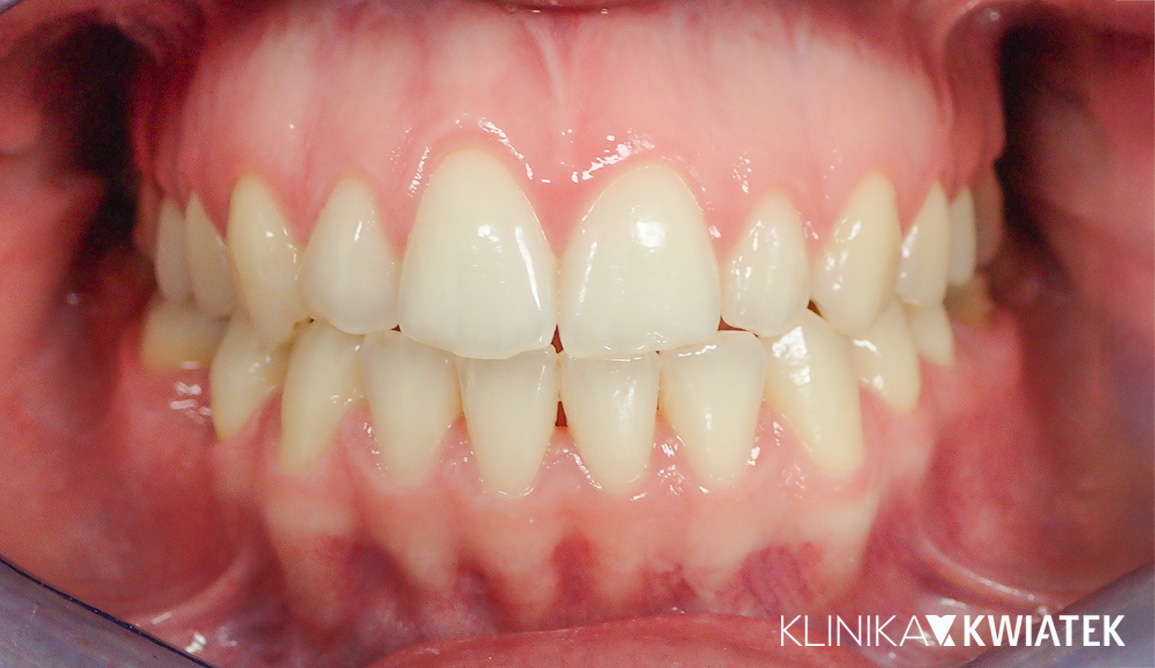

Uśmiech, który zmienia wszystko – kompleksowa metamorfoza dzięki korekcie wady zgryzu i estetycznej przebudowie

Pacjentka zgłosiła się z powodu napięć mięśniowych, zgrzytania zębami i dolegliwości ze strony stawów skroniowo-żuchwowych. Rozpoczęto terapię od szyny relaksacyjnej i fizjoterapii, a następnie wdrożono leczenie ortodontyczne oraz kompleksową odbudowę protetyczno-estetyczną. Efekt końcowy to nie tylko zdrowy zgryz i brak dolegliwości bólowych, ale także piękny, naturalny uśmiech.